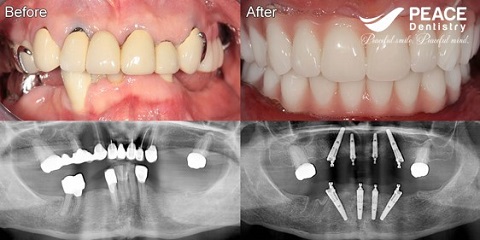

(All on 4 for both upper and lower jaw, patient used removable denture for 12 years)

(All on 4 for patient after 7 year using porcelain bridge)

(Missing all teeth on both jaw, traditional implant for upper jaw and all on 4 for lower jaw)

(All on 4 for both upper and lower jaw)